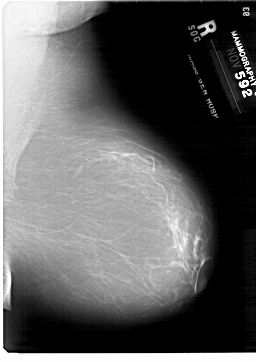

A_1876_1.LEFT_CC

LEFT_CC LINES 6871 PIXELS_PER_LINE 4771 BITS_PER_PIXEL 12 RESOLUTION 43.5 OVERLAY

FILE: A_1876_1.LEFT_CC.OVERLAY

TOTAL_ABNORMALITIES 1

ABNORMALITY 1

LESION_TYPE MASS SHAPE LOBULATED MARGINS MICROLOBULATED

ASSESSMENT 4

SUBTLETY 3

PATHOLOGY BENIGN

TOTAL_OUTLINES 1

BOUNDARY